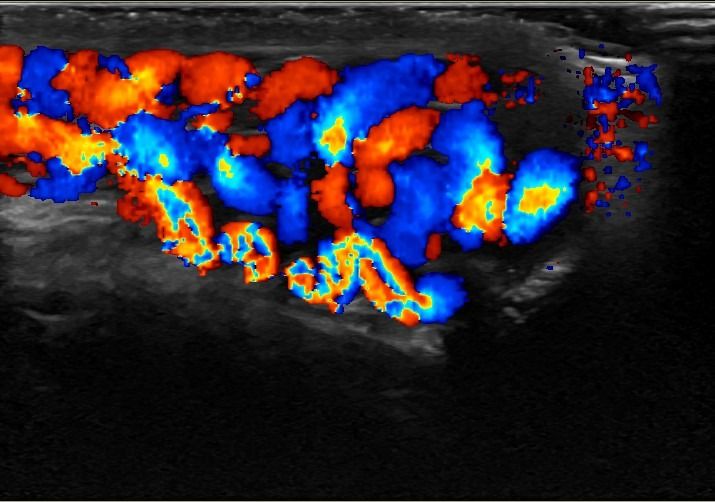

Η μελέτη με Έγχρωμο Doppler παρέχει κρίσιμες πληροφορίες σχετικά με την αγγείωση των όρχεων, ανιχνεύοντας αποκλεισμούς συστροφής ή φλεγμονές, όπως η ορχίτιδα.

Η δοκιμασία Valsalva σε συνδυασμό με το Έγχρωμο Doppler αποτελεί ένα από τα διαγνωστικά εργαλεία για την ανίχνευση της κιρσοκήλης, προσθέτοντας ένα επιπλέον επίπεδο ακρίβειας στη διάγνωση.